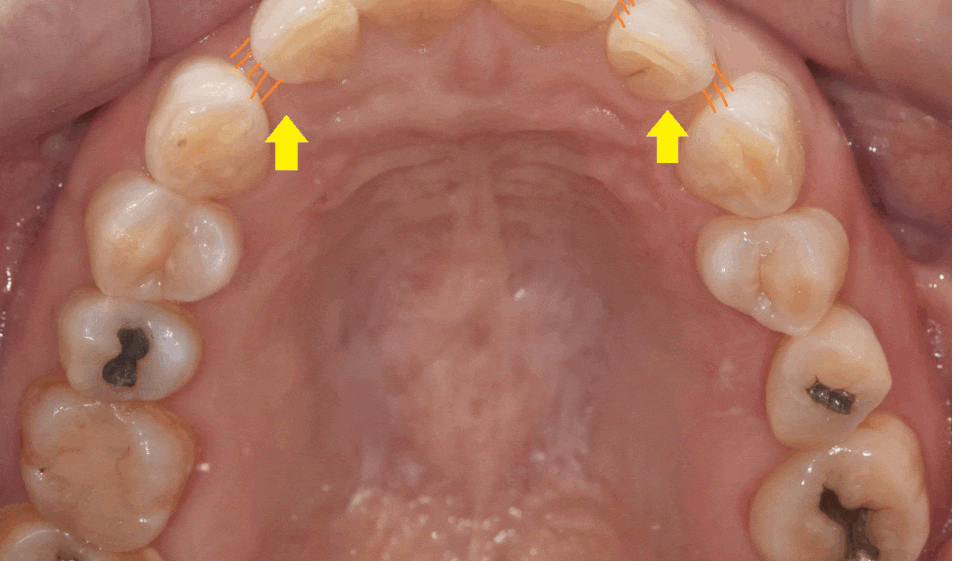

고덕동 교정치과를 찾아오신 40대 여성환자분입니다.

나이가 들수록 치아가 더 벌어지는거 같은데

교합(씹는 부분)은 잘 맞는데

오늘 환자분처럼 앞니 사이 틈이 있어서 보기 싫거나

약간의 삐뚤빼뚤함을 가지고 있을 때 진행합니다.

약간의 치아 사이 공간이 있는 경우

치아를 앞으로 조금씩 움직여 공간을 메꾸면 되기 때문에

치아 삭제없이 앞니 부분교정이 가능합니다.